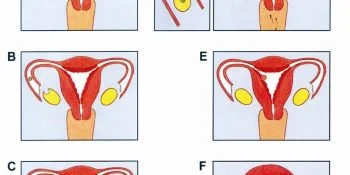

Hamilelik Nasıl Oluşur?

Hamilelik Nasıl Oluşur?Hamilelik, spermin bir yumurta ile buluşması ve döllenmesi ile başlar. Döllenmiş yumurta daha sonra rahmin …